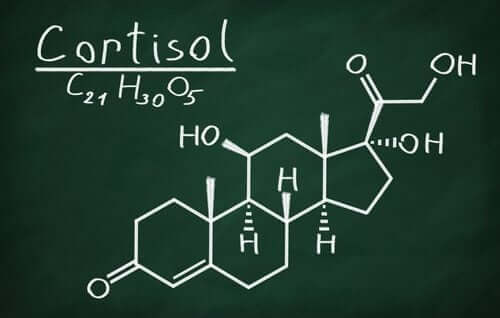

- 쿠싱 증후군: 코르티솔 호르몬 수치가 정상보다 높아지는 상태이다.

이중 초점이나 시력에 문제가 있는지를 먼저 검사한다. 측면 또는 주변 시력 상실과 특정 영역에서 제대로 볼 수 있는지 등에 대해서도 검사를 한다. 그다음 내분비 기능 분석으로 호르몬이 과다 생성되는지 이례적인 점은 없는지 등을 본다. 코르티솔 수치, 쿠싱 증후군, 성장 호르몬 등에 대한 검사도 한다.